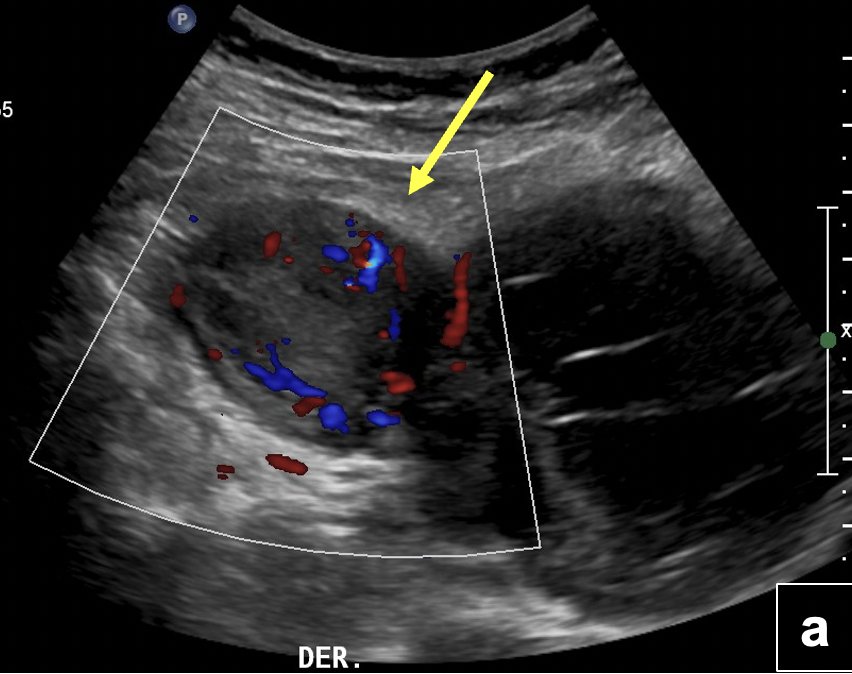

US de abdomen y pelvis: (a) Engrosamiento nodular solido del íleon distal (flecha) vascularizado al Doppler color, (b) el que se continua con imagen quística compleja de gran tamaño ubicada en la fosa iliaca derecha. (c) Engrosamiento parietal difuso de ileón distal visualizado con transductor de alta frecuencia (flecha)